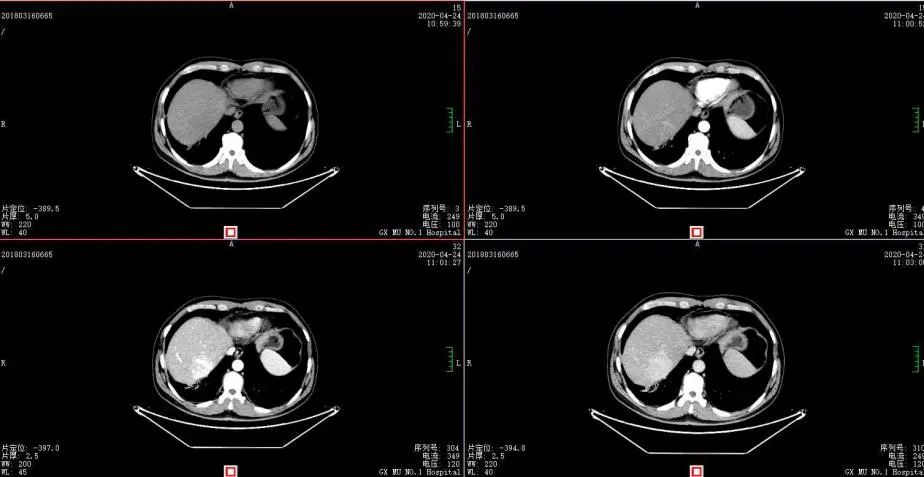

2020年4月复查:持续PR

增强CT示:肝硬化

肝异常强化灶

考虑酒精性肝硬化可能性大,未基线使用替吉奥维持治疗。

胃癌并肝转移化疗后,肝内转移灶大致同期;

慢性肝病,脾大、门脉高压(食管下段-胃底静脉曲张);

双肾小囊肿;

右肺中叶外侧段、左肺上叶下舌段及右肺下叶后基底段慢性炎症;

右肺上叶前段实性微小结节,炎性结节?建议定期复查;

纵隔淋巴结转移瘤,复查大致同前。